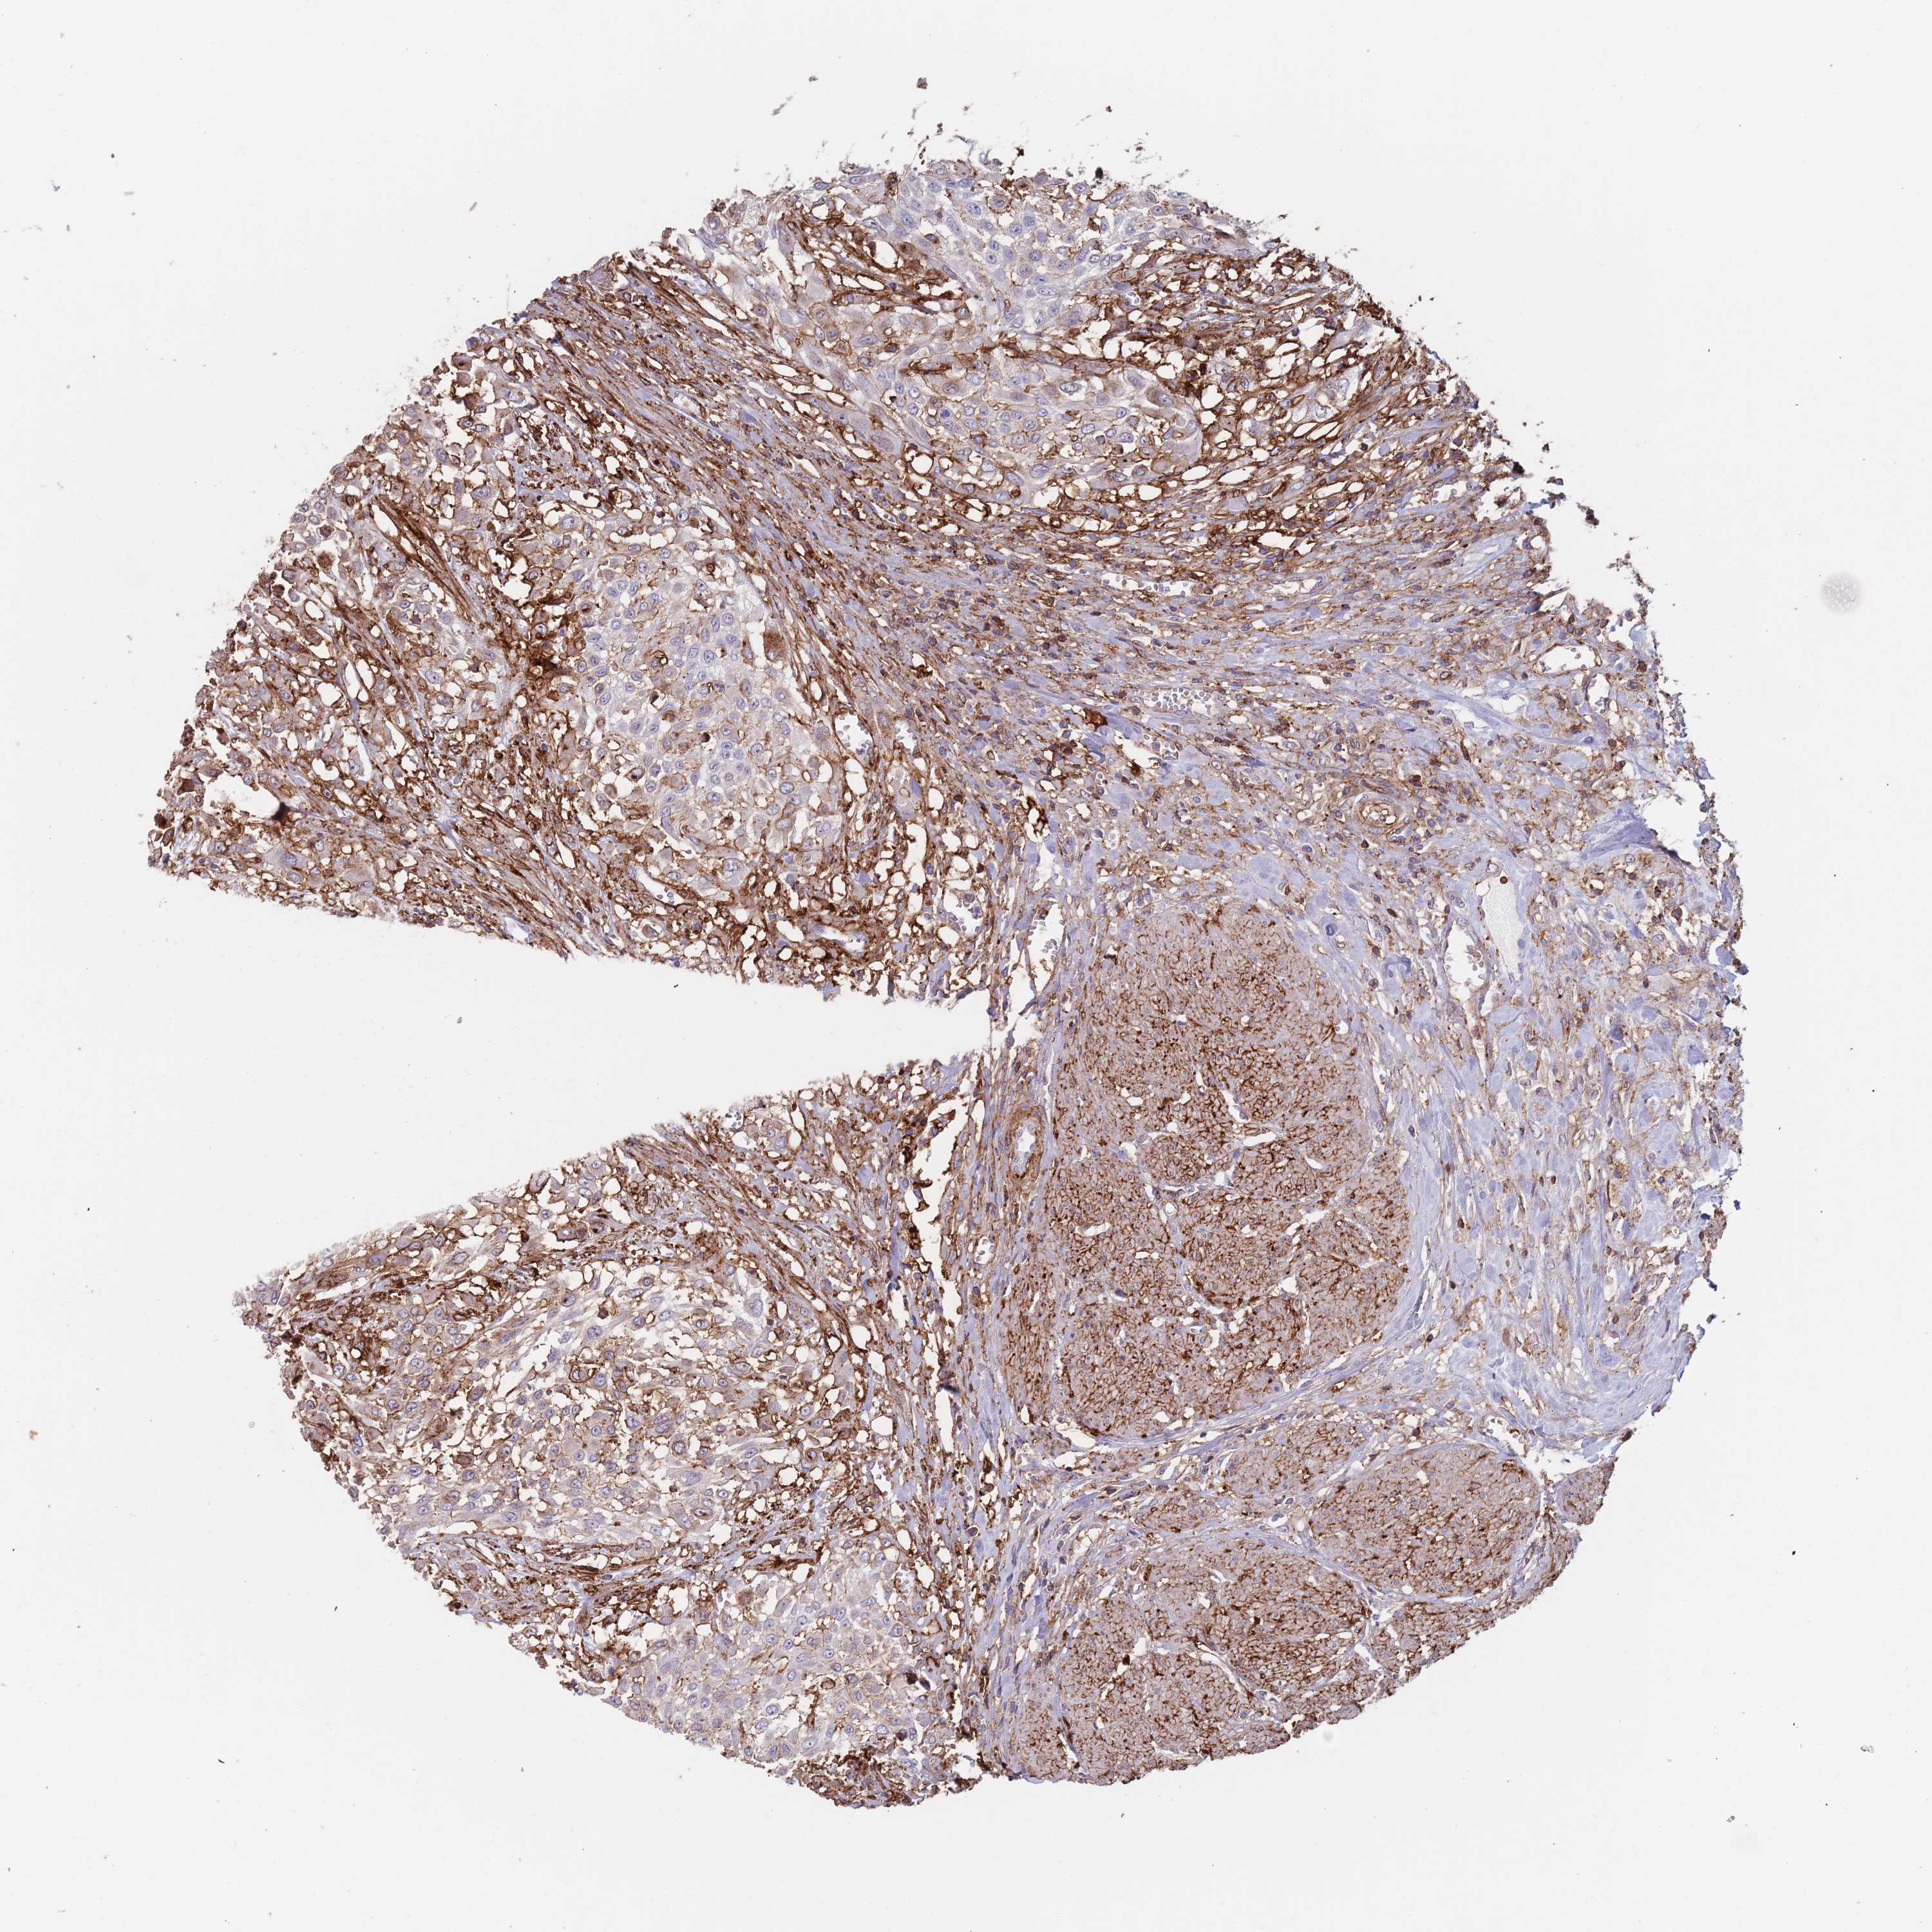

UROTHELIAL CANCER - Protein expressioni

A mouse-over function shows sample information and annotation data. Click on an image to view it in a full screen mode. Samples can be filtered based on level of antibody staining by selecting one or several of the following categories: high, medium, low and not detected. The assay and annotation is described here.

Antibody stainingi

Antibody staining in the annotated cell types in the current human tissue is reported as not detected, low, medium, or high, based on conventional immunohistochemistry profiling in selected tissues. This score is based on the combination of the staining intensity and fraction of stained cells.

Each image is clickable and will lead to virtual microscopy that enables deeper exploration of all samples and also displays staining intensity scores, fraction scores and subcellular localization as well as patient and tissue information for each sample.

Antibody HPA049939

Staining

High

Medium

Low

Not detected

Intensity

Strong

Moderate

Weak

Negative

Quantity

>75%

75%-25%

<25%

None

Location

Nuclear

Cytoplasmic/membranous

Cytoplasmic/membranous,nuclear

Urothelial carcinoma, Low grade

Urothelial carcinoma, High grade

Urothelial carcinoma, NOS